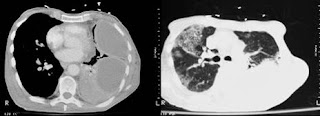

In ultimele luni, medicamentele pentru disfunctiile erectile au devenit un subiect fierbinte de discutie. De cand barbatul de 44 de ani a facut public faptul ca si-a pierdut auzul dintr-o data, au mai existat inca 29 de rapoarte de pierderi de auz in randurile barbatilor, dupa ce acestia au luat pastile Cialis, Levitra si Viagra. Din nefericire, leziunile la nivelul auzului sunt permanente. Ceea ce este mai tulburator este faptul ca incep sa se adune si cazuri de pierderi de vaz in aceleasi conditii.